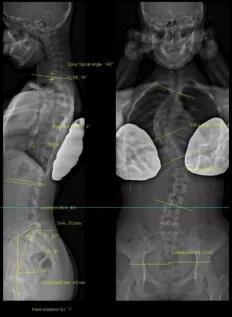

法國(guó)EOS X射線影像采集系統(tǒng)

?諾貝爾物理學(xué)獎(jiǎng)的新型X射線探測(cè)技術(shù);

?實(shí)現(xiàn)了人體1:1真實(shí)成像;

?是非拼接全脊柱、全下肢一次性成像X線設(shè)備;

?僅需0.05mSv(約一張胸片的劑量)即可完成全脊柱正側(cè)位成像。

?正側(cè)位全長(zhǎng)影像一次掃描成像的優(yōu)點(diǎn):負(fù)重位正交同步拍攝、線性掃描1:1全長(zhǎng)片、動(dòng)態(tài)自動(dòng)增益控制;

?雙球管正側(cè)位同步拍攝:一次掃描同時(shí)獲得正、側(cè)位影像,消除兩次拍攝的系統(tǒng)誤差;

?精準(zhǔn)的線性掃描:幫助醫(yī)生對(duì)脊柱、關(guān)節(jié)等相關(guān)骨骼疾病進(jìn)行術(shù)前診斷、制定手術(shù)計(jì)劃、評(píng)估手術(shù)效果、跟蹤隨訪以及相關(guān)科研工作;

?不失真高質(zhì)量圖像:全身視圖1:1。

脊柱側(cè)彎